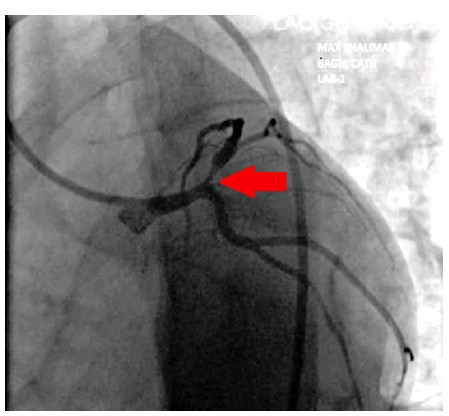

Wellens syndrome is a distinct electrocardiographic (ECG) finding that reflects critical narrowing of the proximal left anterior descending (LAD) coronary artery. First identified in 1982, this pattern typically appears in patients with a history of unstable angina, especially during pain-free intervals. Recognizing this syndrome is vital, as it signals a high risk for imminent anterior wall myocardial infarction if not treated promptly. The syndrome is classified into two types based on T wave morphology. Type A, which features biphasic T waves most prominently in leads V2 and V3, can be particularly challenging to identify. These subtle ECG changes are often overlooked, especially when the patient is not actively experiencing chest pain, which increases the risk of misdiagnosis or delayed treatment. Such oversight can lead to rapid deterioration and serious cardiac complications, including extensive myocardial infarction. In this case report, we present a patient with type A Wellens syndrome, where the early ECG showed only mild biphasic T wave abnormalities that were initially missed. This diagnostic oversight delayed appropriate cardiologic intervention and emphasized the importance of vigilance in evaluating atypical or transient ECG changes. Early identification of Wellens syndrome, even in asymptomatic phases, is critical to guiding appropriate management and preventing life-threatening outcomes. Clinicians, particularly in emergency medicine settings, should be aware of these subtle yet significant ECG markers.